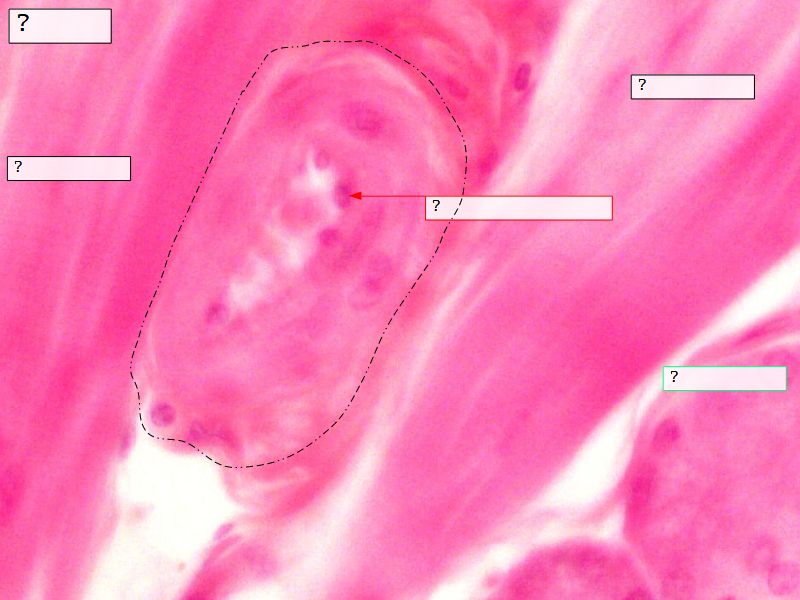

Fill in all the missing labels, and assess as you move through the slides. Answers on the down slide. It is important to do this using pen and paper, and not just glance through the images.